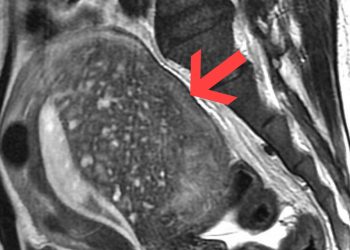

Diagnosis and Medical Imaging of Adenomyosis Diagnosing adenomyosis...